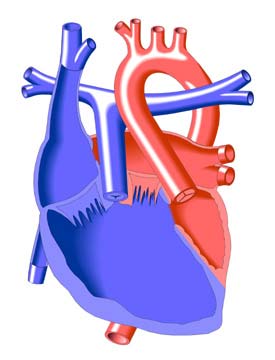

Um transplante cardíaco é uma operação em que um coração doente e falho é substituído por um coração doador saudável….

A tetralogia de Fallot, que é uma das cardiopatias congênitas mais comuns, compreende obstrução da via de saída do ventrículo…

Quando a doença valvar progride ao ponto em que o tratamento médico não proporciona alívio dos sintomas, um médico…

A síndrome do coração esquerdo hipoplásico é um dos defeitos cardíacos mais complexos vistos no recém-nascido e continua sendo provavelmente…